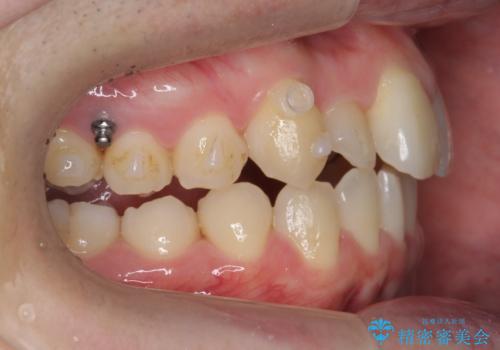

右上の奥歯を後ろに移動して、前に出すスペースを確保してから並べました。

奥歯を後ろに送るために、矯正用インプラントを使用しています。

- 104.5万円(マウスピース矯正 93.5万円、矯正用スクリュー11万円)費用は治療当時の料金となります